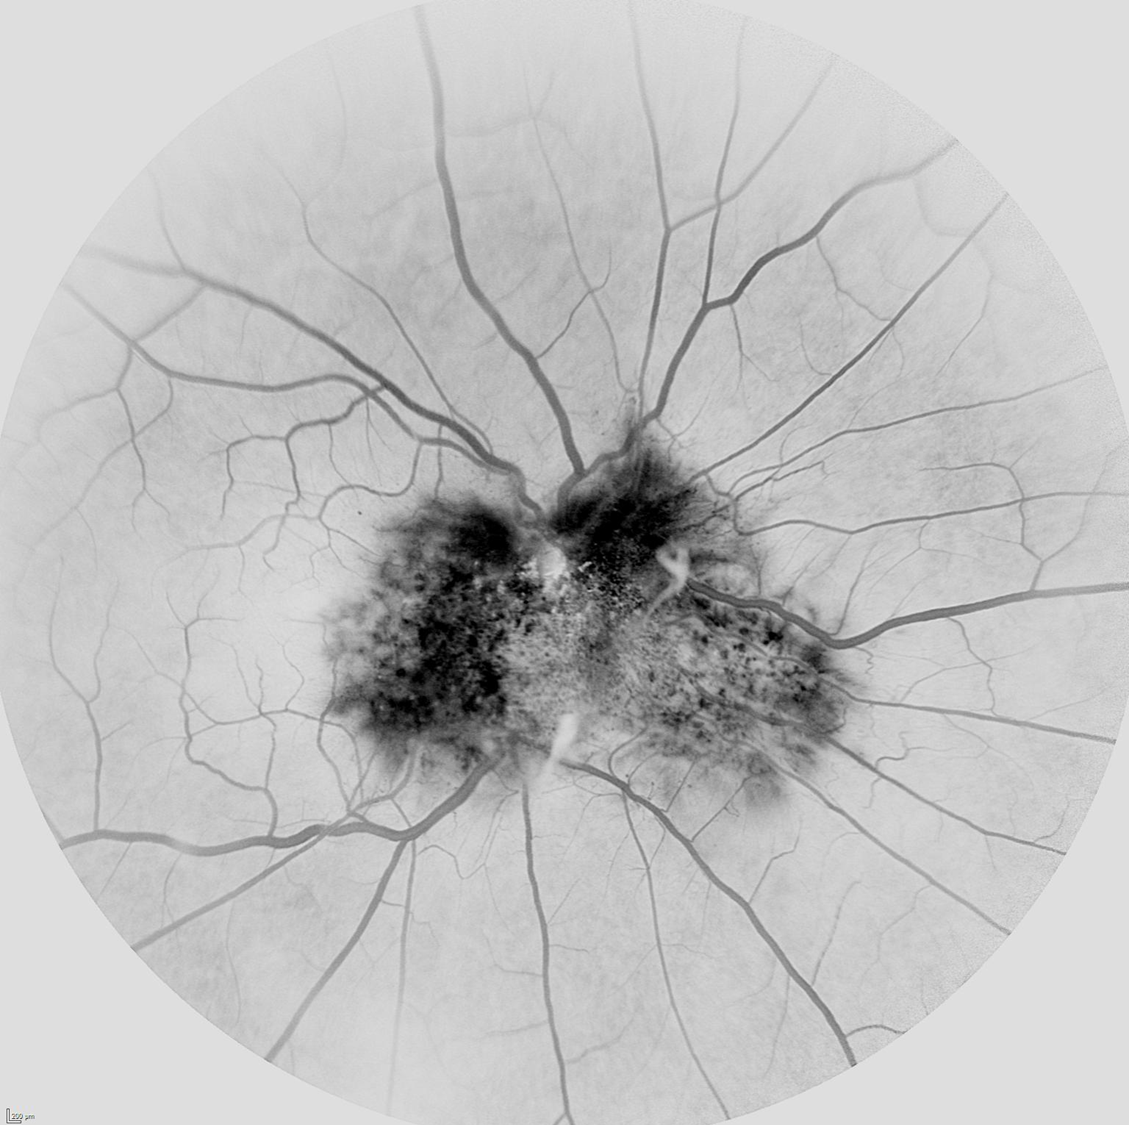

Angiografía fluoresceínica en hamartoma combinado de retina y epitelio pigmentario modo negro sobre blanco

La angiografía puede ayudar bastante en el diagnóstico observándose en las fases precoces hipofluorescencia en relación al grado de hiperpigmentación del tumor, tortuosidad vascular y telangiectasias. En la fase media se observan mejor las anomalías vasculares y según avanzan los tiempos los vasos suelen fugar dando lugar a una hiperfluorescencia tardía.